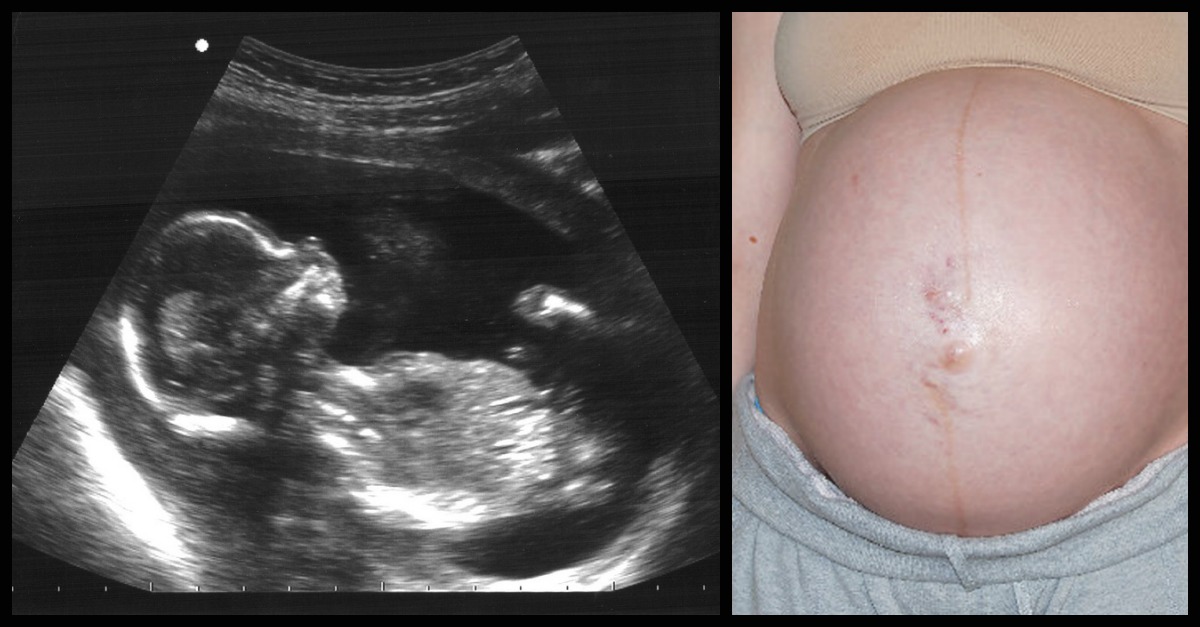

Why Do Babies In The Womb Have Hiccups . What do hiccups in the womb feel like? How to stop fetal hiccups. But unlike newborns and infants, babies in the womb are not. Fetal hiccups happen as your baby's diaphragm moves when they begin practicing their breathing. Other things fetuses do in the womb. So what are fetal hiccups? According to one researcher’s 2012 article in bmc pregnancy and childbirth , it’s suggested that hiccups in utero might be caused by compression of the umbilical cord. Can babies hiccup in the womb? Baby hiccups in the womb feel like small, rhythmic, jerking movements. One such myth is that a baby with hiccups in the womb may indicate potential danger in utero. Quite simply, baby hiccups in the womb are the little movements baby’s diaphragm makes when. In the beginning they may be hard to distinguish from your baby's kicks. A pregnant person may also notice fetal hiccups. Yes, your developing baby can hiccup in utero. Although the exact cause is unknown, some experts believe it may have to do with your baby.